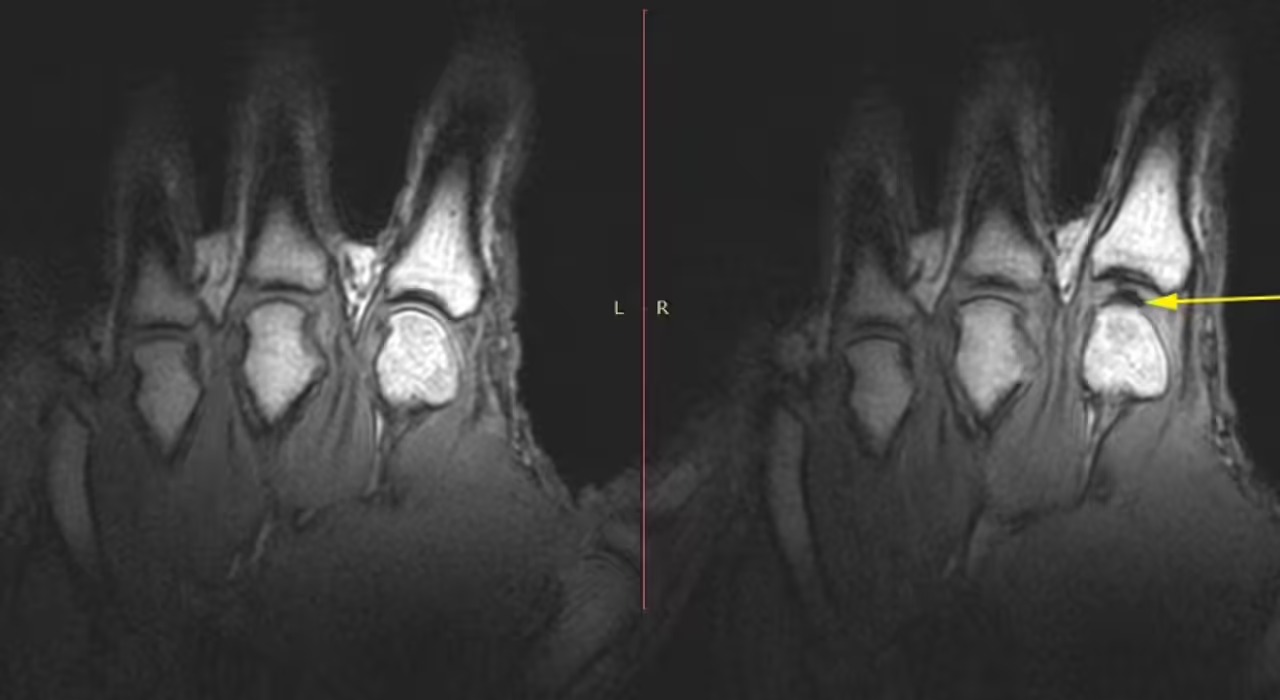

يتفق الباحثون على أن الصوت الناتج عن طقطقة مفاصل الأصابع أو غيرها من المفاصل ناتج عن الغازات، وليس عن احتكاك العظام أو تمزق الغضاريف، استخدمت دراسة واسعة التصوير بالرنين المغناطيسي في الوقت الحقيقي لمراقبة المفاصل أثناء طقطقتها.

وأظهرت الفحوصات أنه عند شد المفصل أو تمديده، ينخفض الضغط داخله فجأة، ولا يستطيع السائل الزلالي، وهو السائل اللزج الذي يُزلق المفاصل، ملء الفراغ المتزايد بالسرعة الكافية، فيتشكل تجويف مملوء بالغاز داخل هذا السائل، تُعرف هذه العملية باسم الاحتكاك النووي، والتشكل السريع لهذا التجويف هو ما يُنتج صوت الطقطقة.

شرح جريج كاوك، الأستاذ في كلية طب إعادة التأهيل بجامعة ألبرتا بكندا، عملية طقطقة الأصابع وفقًا لموقع ساينس أليرت، قائلاً: “عندما تفعل ذلك، يمكنك أن ترى بوضوح شديد ما يحدث داخل المفاصل، الأمر أشبه بتكوين فراغ، فعندما تنفصل أسطح المفصل فجأة، لا يتوفر المزيد من السوائل لملء حجم المفصل المتزايد، لذلك يتم إنشاء تجويف وهذا الحدث هو ما يرتبط بالصوت".